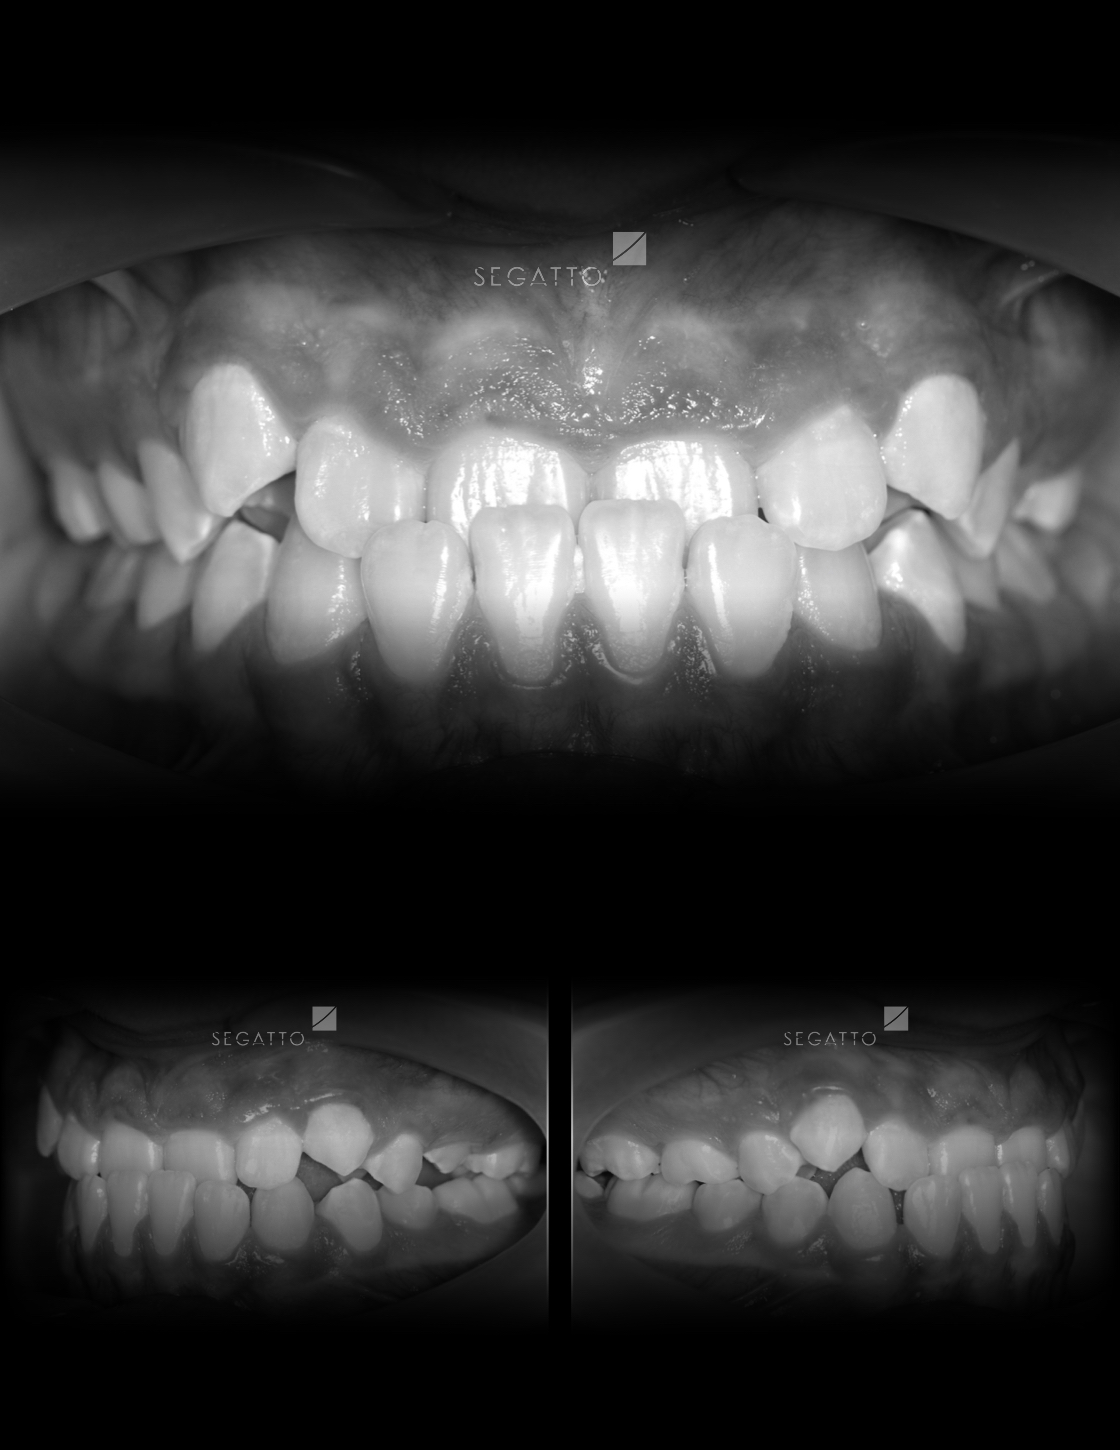

Orthodontics

Cases